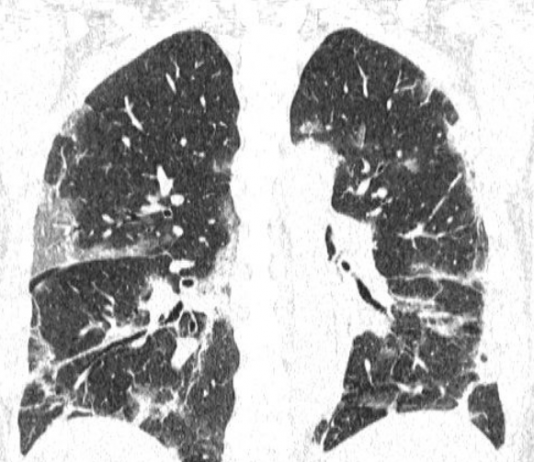

Paziente uomo, 61 anni, con anamnesi patologica remota negativa.

Anamnesi patologica prossima contatto nella terza settimana di...